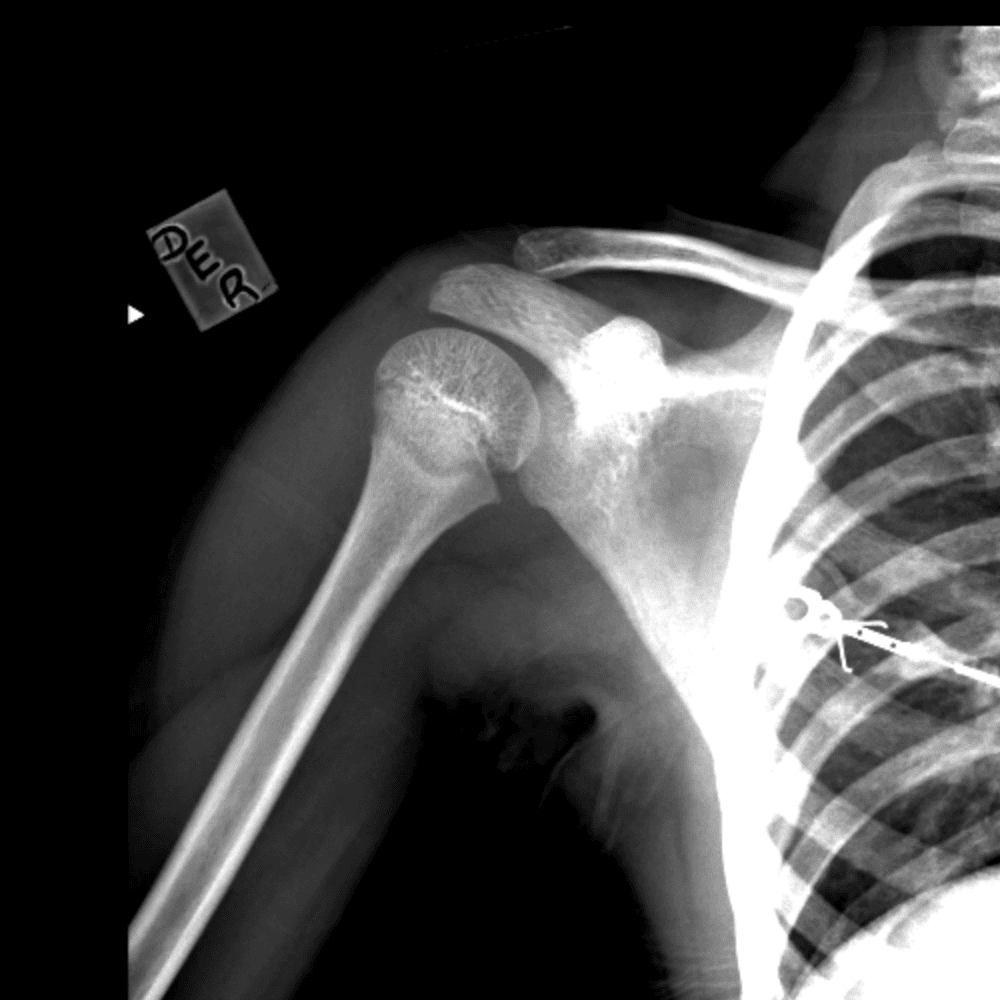

Simuliert den Dienst durch subtile oder schwierige Fälle und einige Normalbefunde.

30 Fälle